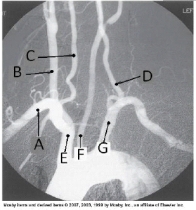

Letter D in the angiographic image of the aortic arch and its branches below is the _____ artery.

A) innominate (brachiocephalic)

B) L common carotid

C) L subclavian

D) L vertebral

Letter E in the angiographic image of the aortic arch and its branches below is the _____ artery.

Letter G in the angiographic image of the aortic arch and its branches below is the _____ artery.

Letter A in the angiographic image of the aortic arch and its branches below is the _____ artery.

B) R common carotid

C) R subclavian

D) R vertebral

Letter F in the angiographic image of the aortic arch and its branches below is the _____ artery.

Letter B in the angiographic image of the aortic arch and its branches below is the _____ artery.

Letter C in the angiographic image of the aortic arch and its branches below is the _____ artery.